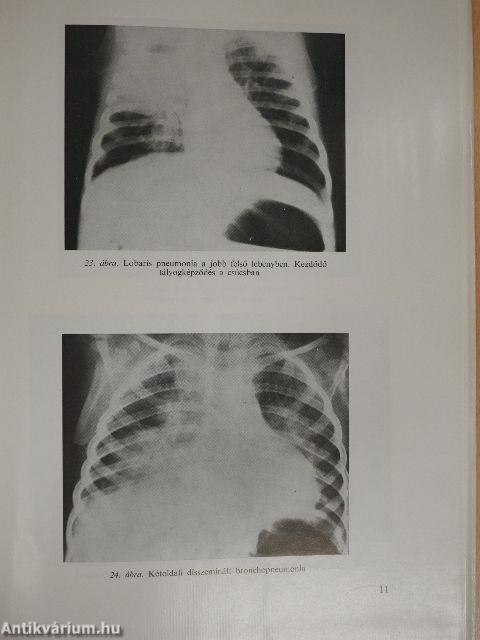

Megjegyzés: A könyvet fekete-fehér fotók illusztrálják.

Pneumonia. Tüdőgyulladás83